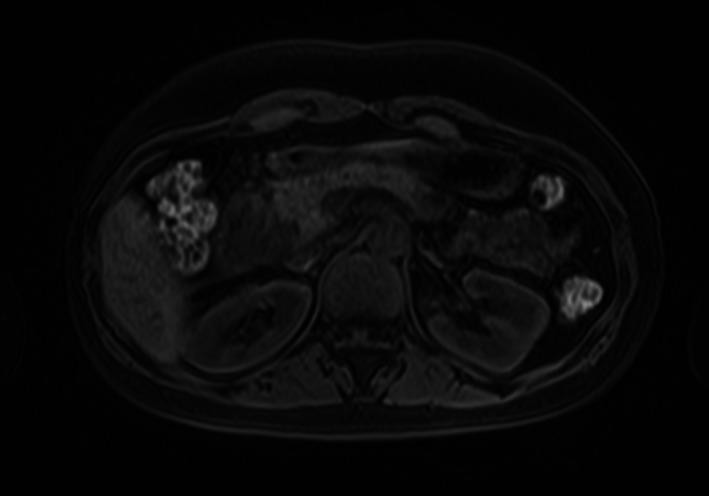

A 45‐year‐old female patient, with no relevant clinic history, had 15 days of abdominal pain in the right upper quadrant, and abdominal ultrasound was performed to rule out cholelithiasis; instead, a peripancreatic adenopathy was observed, confirmed by abdominal computed tomography (CT) (Fig. 1, CT scan.tiff) and magnetic resonance (MRI) (Fig. 2, MRI.tiff). She was then referred to the gastroenterologist to undergo an EUS and rule out pancreatic tumor.

Figure 2.

Abdominal magnetic resonance imaging shows a solid lesion located at the peripancreatic level adjacent to the head of the pancreas.

On imaging, pancreatic tuberculosis most often presents as a solid or cystic lesion. Abdominal CT shows the presence of a low‐density mass with ring enhancement, which is considered a characteristic finding. T1‐weighted fat‐suppressed MRI shows hypointense pancreatic TB lesions, while T2‐weighted images show heterogeneous signal intensities. With FDG PET‐CT images, it is difficult to distinguish tuberculous lymphadenitis from pancreatic malignancy because both conditions can result in increased fluorodeoxyglucose (FDG)‐positron emission tomography uptake. 9 , 10